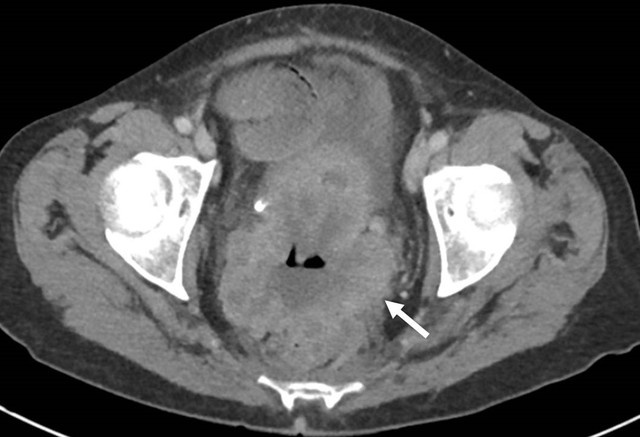

ung thu dai trang anh 1

Ung thư đại tràng trên phim chụp CT bụng (mũi tên). Ảnh: SKĐS.